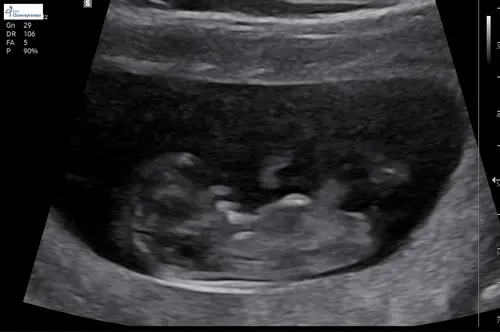

13 weken. Wat denken jullie?

De echoscopist wilde niks zeggen vanwege de 13w echo maar zei dat ze het du ...

Jongen

De nub is hier goed te zien. Denk boy maar ben niet zeker vanwege lighoudin ...

Dank voor je reactie! Het is een video opname, hier nog een paar screenshots.